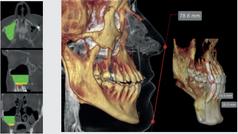

Maximum flexibility for your diagnoses Hyperion X9 pro is fully configurable and its modular and scalable design makes it possible to transition from a basic to a more advanced version in an easy and costeffective manner. An extraordinary platform that adapts to the needs of your dental practice thanks to the 2D PAN/CEPH sensor, which can be easily relocated, and the reversible teleradiographic arm which can be installed on both sides Moreover, the standard 2D sensor can be replaced with the innovative direct conversion DCIII sensor to provide SuperHD images with low doses The most versatile extra-oral 3-in-1 imaging device on the market. Perfect for ultra-high quality 2D and 3D exams with very low doses

FOVs with a 10 cm diameter are essential for the study of impacted third molars because, in an adult of medium build, the distance between the third molars on the left and right, including the respective roots, the alveolar process and the surrounding bone, is at least 9 cm Reduced fields of view are useful when analysing impacted or supernumerary teeth in order to restrain the dose to the region of interest For a correct treatment planning it is indeed crucial to determine the actual position (vestibular or palatal) This is only possible with a 3D analysis, even at a very low dose, with the QuickSCAN protocol The complete 13 x 16 cm field of view allows for an accurate assessment of the upper airways, which is often useful to complete the investigation for an orthodontic treatment that does not neglect ENT problems.

Position the equipment directly on the 3D model, combine it with the STL data from intraoral scanners and define the final prosthetic project With the advanced implant planning tools* you will be able to operate safely thanks to accurate information on the amount of bone and the distance from the surrounding anatomical structures, such as the mandibular canal, defining a minimum safety distance